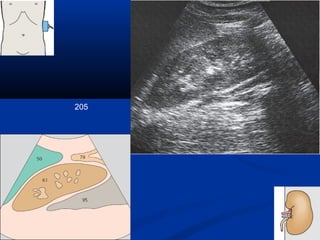

205